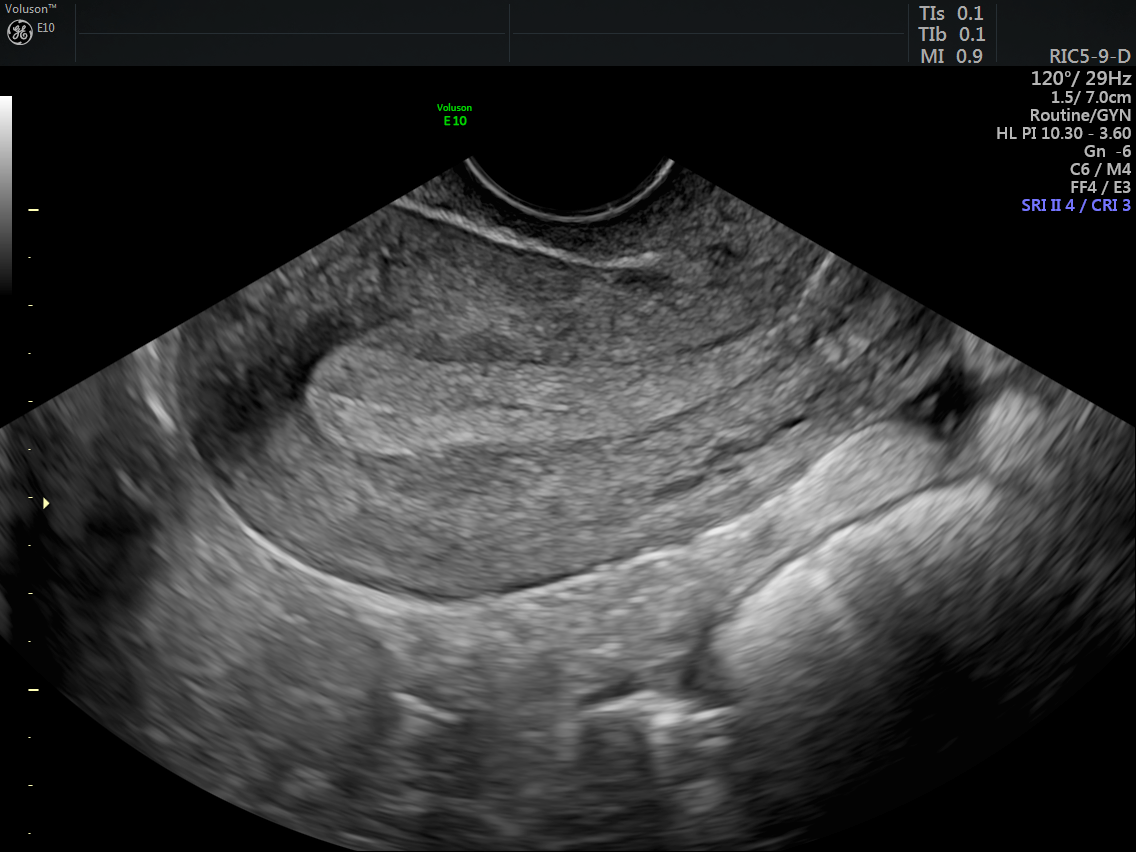

from www.volusonclub.net

endometrial thickness is a commonly measured parameter on routine gynecological ultrasound and mri. transvaginal sonography (tvs) is routinely performed as part of a pelvic sonogram in postmenopausal women, and images of the. the endometrium gradually thickens throughout menstrual cycle phases: secretory phase = luteal phase. Gynecologists prefer the ovarian descriptor, i.e. During this secretory phase, endometrial thickness is. about 14 days into a person’s cycle, hormones trigger the release of an egg.

Using Endometrial Cancer Ultrasound for Earlier Detection Empowered Thickened Endometrium Secretory Phase secretory phase = luteal phase. about 14 days into a person’s cycle, hormones trigger the release of an egg. the endometrium gradually thickens throughout menstrual cycle phases: During this secretory phase, endometrial thickness is. Gynecologists prefer the ovarian descriptor, i.e. transvaginal sonography (tvs) is routinely performed as part of a pelvic sonogram in postmenopausal women, and. Thickened Endometrium Secretory Phase.